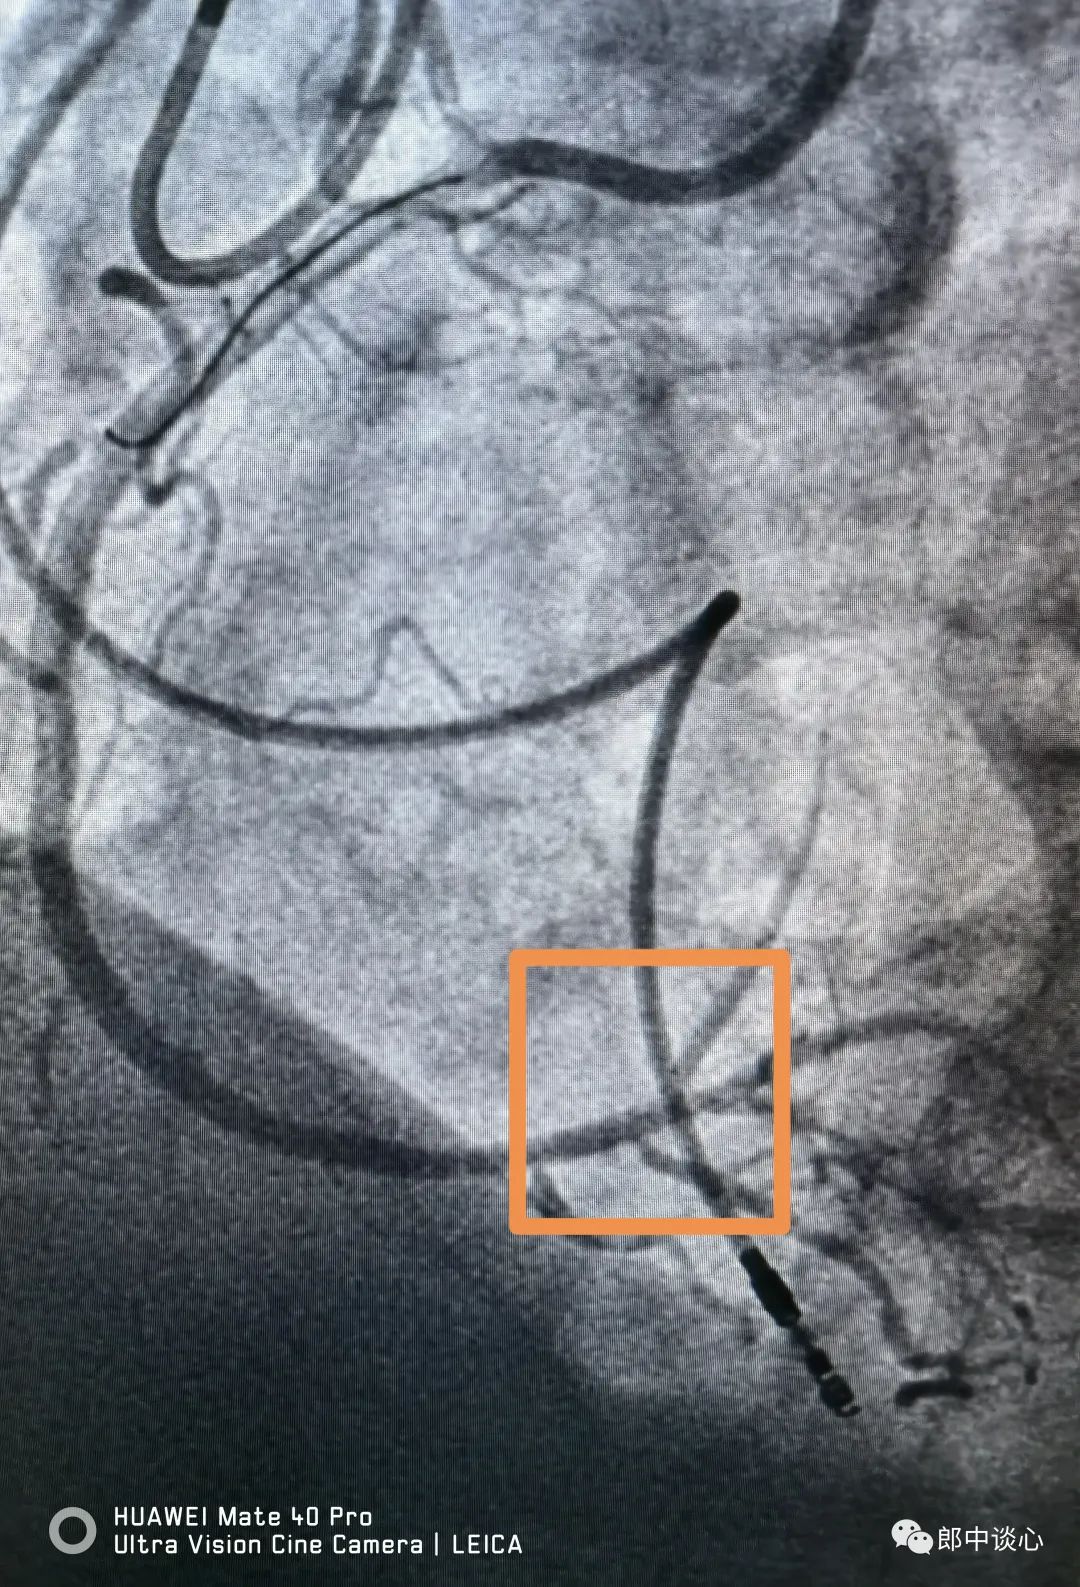

前降支和回旋支完全血运重建后的冠脉似乎又完美如初了!这位病友最值得称道的地方是在一般体检后发现问题,没有不加重视地放过,进一步心脏体检结果发现了问题,并完美解决了问题。